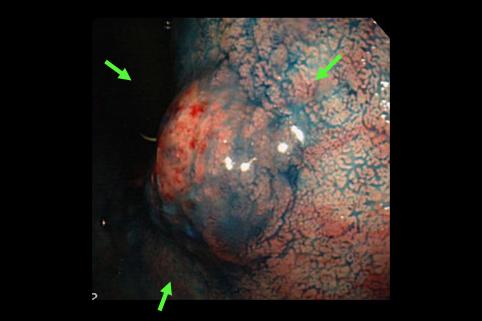

A case of type 0-I early gastric cancer which was histologically mucinous adenocarcinoma and showed a submucosal tumor like appearance.

[ Image ID:11420 ]

Malignant epithelial tumor/Mucinous carcinoma

Stomach/Body

Endoscopy

Type 0/I (I) Protruded type

25 - 29

submucosa